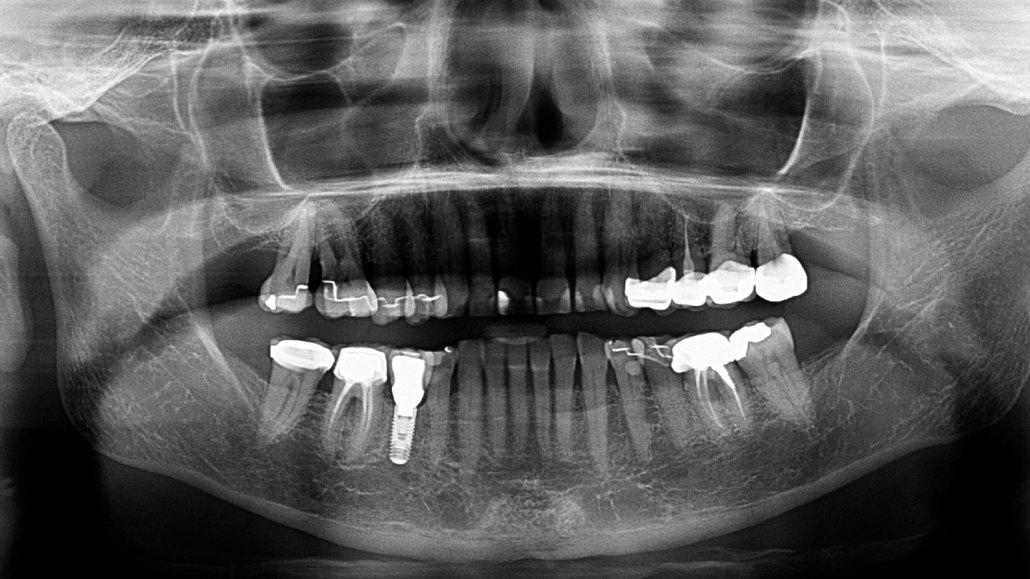

A screw anchors a fake tooth to a person’s lower jaw in this X-ray image. Such dental implants can transmit sound well and could be used as part of a novel hearing aid design.

BSIP/Collection Mix: Subjects/Getty Images Plus